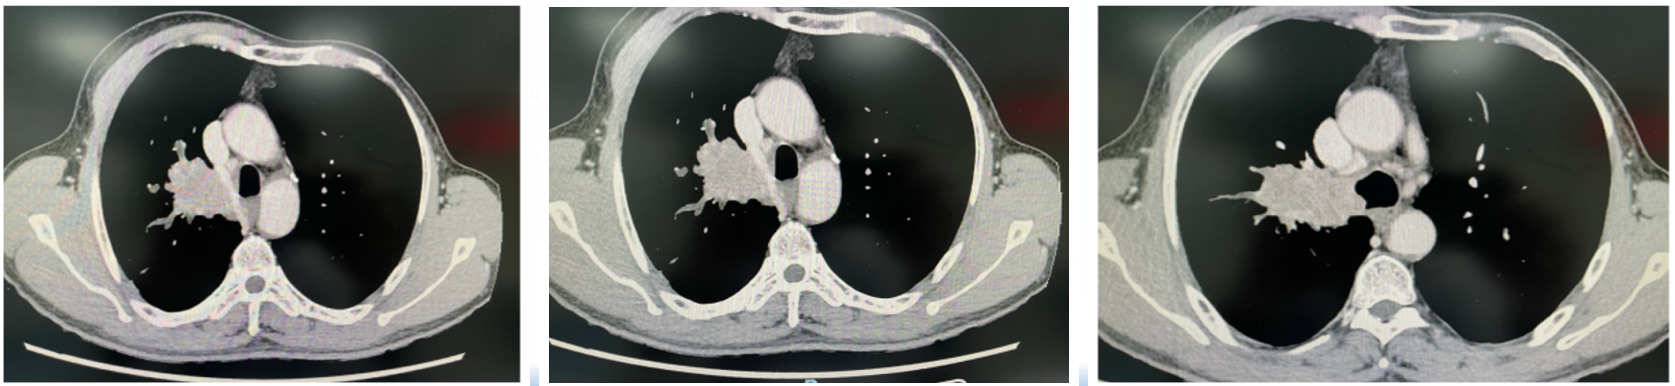

胸部增强CT:右肺门处软组织肿块影,范围约5.6×3.4×4.9cm,累及隆突、右中间支气管、中下叶支气管开口处狭窄;肿物与纵隔胸膜关系密切。考虑肺癌(T4)。纵隔4R、7区多发密度增高淋巴结。左肺门、腹腔及腹膜后未见肿大淋巴结。

影像学评估:

支气管镜评估:

肿瘤退缩,仅粘膜糜烂,右上叶支气管远端部分欠通畅。

活检病理:右中间段支气管和右主支气管被覆假复层纤毛柱状上皮的粘膜组织,伴急、慢性炎细胞浸润。